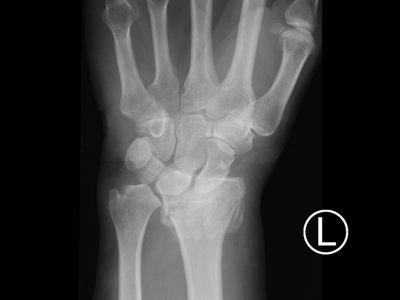

Υπάρχουν 64 οστά στην περιοχή των άνω άκρων – 10 στον ώμο και το βραχιόνιο, 16 στη περιοχή του καρπού και 38 στα χέρια και τα δάχτυλα. Τα κατάγματα της κλείδας και της πηχεοκαρπικής είναι τα πιο συχνά στο άνω άκρο.

5. Κατάγματα πηχεοκαρπικής και άκρας χείρας συμπεριλαμβανομένων καταγμάτων σκαφοειδούς και εξαρθρημάτων στα μικρά οστά του καρπού.

Παρακάτω παρατίθενται ακτινογραφίες καταγμάτων του άνω άκρου που αντιμετωπίζονται με εσωτερική οστεοσύνθεση ή επανορθωτική χειρουργική με αρθροπλαστική.